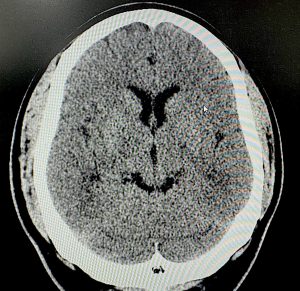

A 2D CT scan demonstrated significant enlargement of the temporalis muscle, including a prominent anterior component.

In surgery, the temporalis muscle thickness at the level of the upper ear measured 15 mm. A combined approach was performed through postauricular incisions, consisting of: